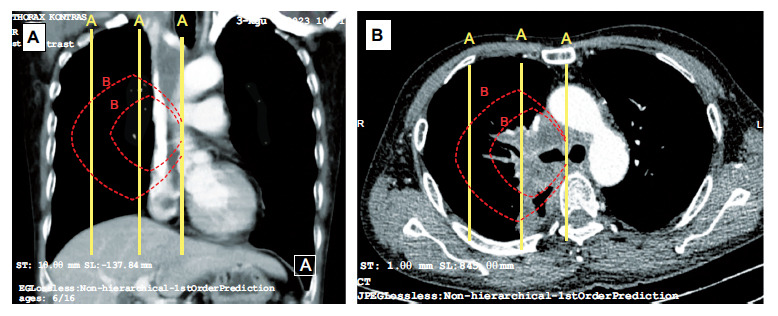

Methods: This was an observational cross-sectional study of PCLTs, defined as tumors in direct contact with hilar structures or located within the inner two-thirds of the hemithorax. We gathered demographic and clinical data, as well as data on bronchoscopy assessment and histopathology type. Tumor stage, symptoms of superior vena cava syndrome, and enlargement of lymph nodes in the paratracheal and subcarinal regions were also documented.

Abstract Image